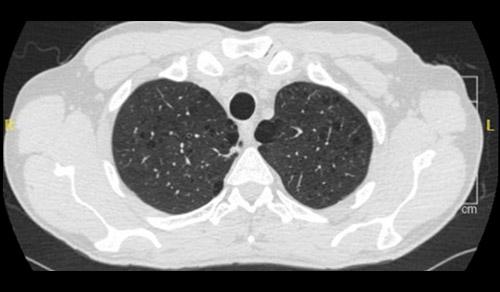

Clinicians from Columbia and Weill Cornell Medicine are at the forefront of pulmonary medicine and lung surgery combine leading-edge therapies with compassionate care for patients with all types and stages of lung disease. Our researchers are contributing to promising advances in acute lung injury, COPD, interstitial lung disease, and pulmonary hypertension.

Pulmonology & Lung Surgery